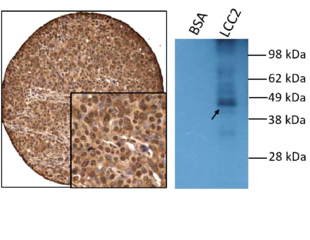

Annexin A3 as a Diagnostic Biomarker and Therapeutic Target for Treating Hepatocellular Carcinoma

Diagnostics

Therapeutic Biologics